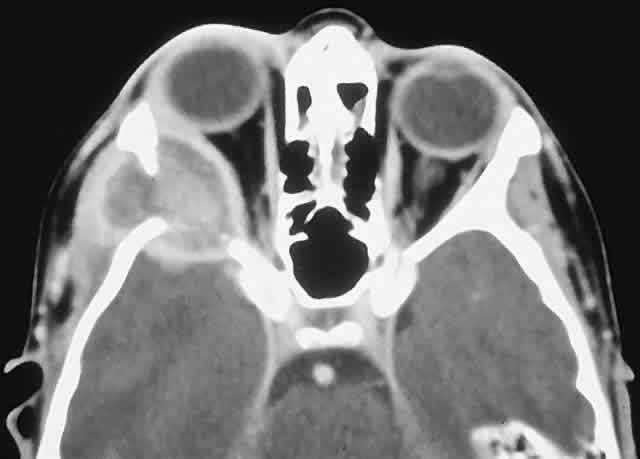

PRESENTATION. A superolateral mass effect encompassing weeks to years is the typical mode of presentation. This leads to inferior globe displacement, proptosis, and diplopia in upgaze (Fig. 5). There may be associated headache or pain; one third of patients recall a prior trauma.70,71

Fig. 5. A 41-year-old man had a 2-year history of left proptosis and headaches. A. Examination found 6 mm of proptosis with 4 mm of inferior ocular displacement. B. CT showed an osteolytic mass arising from the superolateral frontal bone and extending into the orbit. C. Histologically, a classic picture of cholesterol granuloma was apparent, with numerous cholesterol clefts surrounded by granulomatous inflammation containing foreign body giant cells (hematoxylineosin, × 20).

IMAGING. The granuloma arises in the diploë of the frontal bone, causing expansion and eventually erosion of the inner and outer tables. CT reveals it to be osteolytic, with a density equivalent to brain, and occasional intralesional bone fragments.72 Mature lesions display high T1 and T2 signal intensities on MRI.73,74 The most commonly evoked differentials in this setting are dermoid cysts and lacrimal gland carcinomas.

HISTOPATHOLOGY. These cysts usually contain yellow-brown viscous material with friable tissue and porous bone at the periphery. Histologically, the principal feature is the dominance of cholesterol clefts surrounded by granulomatous inflammation with conspicuous foreign body giant cells. A variable fibrous stroma is present and usually contains extensive blood-derived debris in the form of extracellular and intracellular hemosiderin as well as more recent hemorrhage.70,75